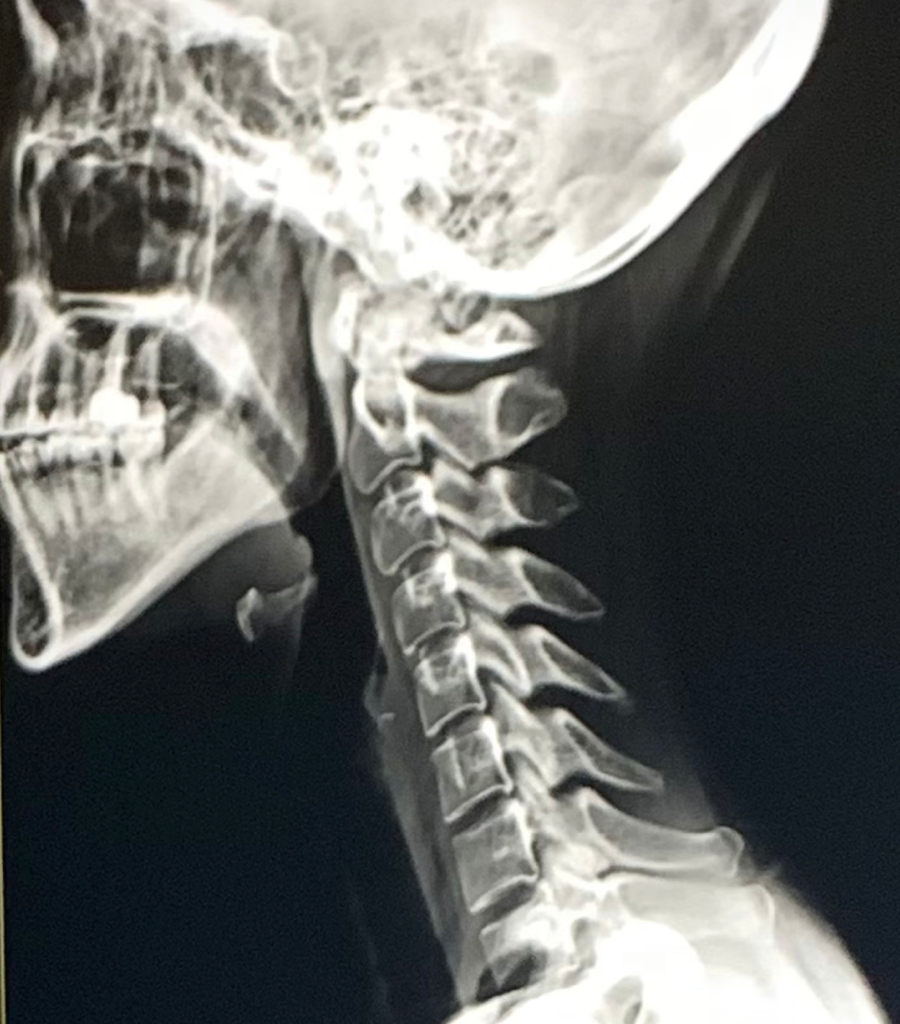

말씀주신것은 hyoid bone 목뿔뼈라고하는 정상적인 뼈입니다.

말씀하신 뼈는 정상적으로 존재하는 뼈입니다. 이빨이 난 것이 아니며 설골이라는 뼈가 엑스레이에서 관찰되는 것입니다. 정상적인 소견입니다.

현재 엑스레이상 발견되는 뼈 부위는 설골(hyoid bone)입니다. 이전 해당 뼈는 정상적인 구조물로 수술과는 관계를 찾기는 어렵겠습니다.

치아로 단정지을 수 없지만 턱 아래에 X-ray상 석회화와 같은 병변이 관찰되고 있습니다.